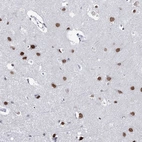

Immunohistochemical staining of human cerebral cortex shows strong nuclear positivity in neuronal cells.